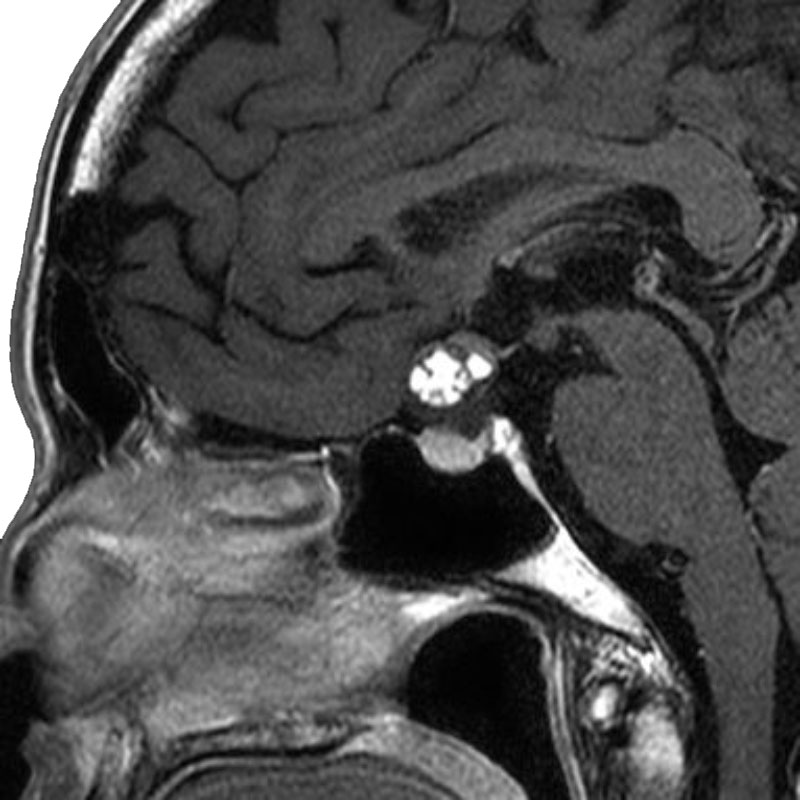

三叉神経鞘腫

摘出術

南田/野本